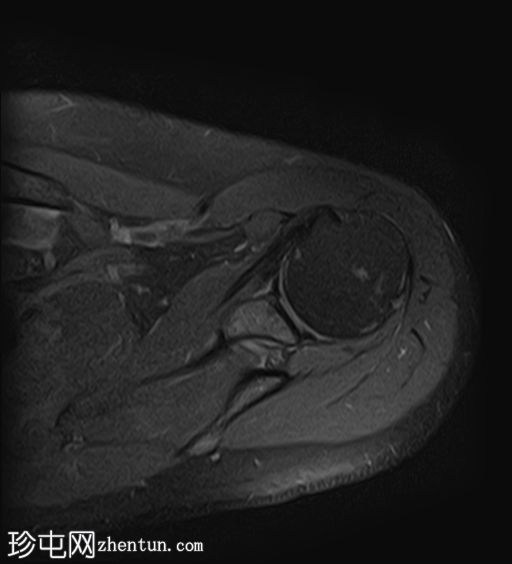

轴位PD加权像

脂肪抑制像

冈上肌腱上部纤维可见约25 x 1.2 mm的低信号肌腱内病变,符合钙化性肌腱炎的影像学表现

冈上肌腱滑囊侧纤维可见液体信号增高,符合肌腱病

II型肩峰(弯曲型)

肩峰下滑囊内可见轻度液体信号,提示轻度滑囊炎